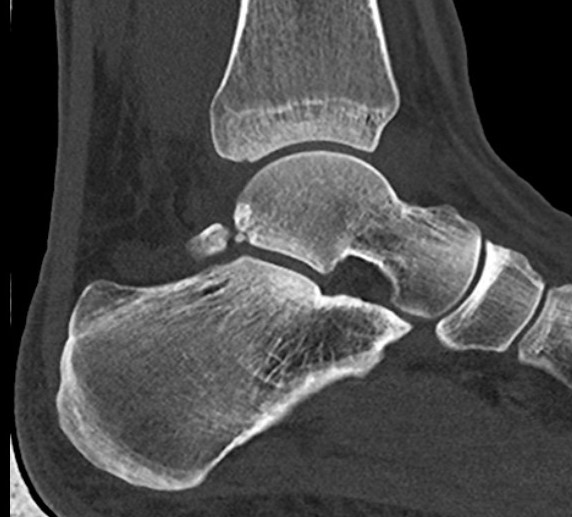

CT

Os trigonum

Fractured Stieda process

Os trigonum with osteochondral fracture posterior tibia